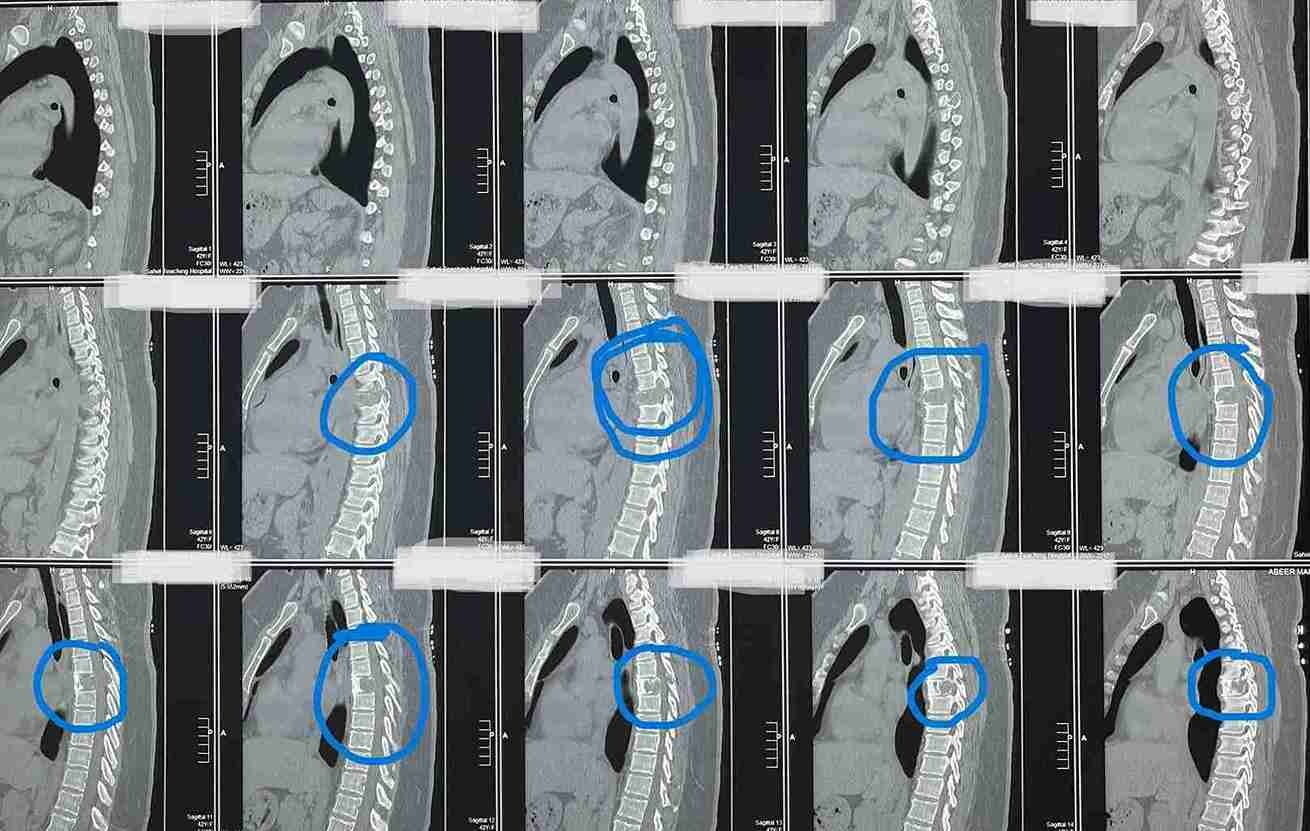

بعد عمل الاشعات تبين وجود ورم التكيس الدموي المتمدد بالفقرة الصدرية السادسة.

وذلك موضح بصور الاشعات قبل وبعد الجراحة . وقد تحسنت المريضة واستعادت كامل الوظايف العصبيىة واصبحت تمارس حياتها بصورة طبيعية.